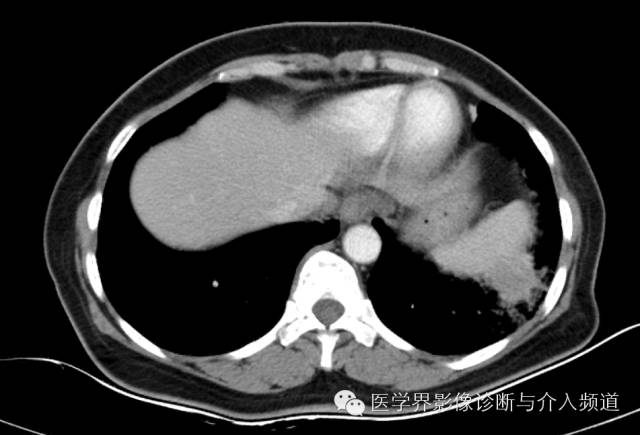

左下肺硬化性血管瘤1例CT影像表现

女性,59岁,三天前无诱因出现咳嗽,痰中带血,量不多,无气短喘息,无胸痛,无盗汗自汗,自发病以来,无发热寒战,无心悸,胸憋,无咳浓臭痰,无头痛呕吐,来我院就诊,行CT检查。

左肺下叶可见软组织密度肿块影,形态不规则,边界不光整,与胸膜粘连不清,周围肺组织呈磨玻璃密度改变,病变内部不均匀强化,低密度区不强化。

硬化性血管瘤